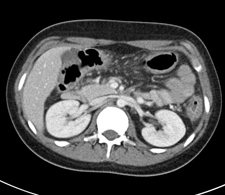

Abdominal CT scanRadiation is simply energy traveling in the form of waves. Radiation is not always bad – in fact, it’s everywhere. We encounter radiation every time we are exposed to sunlight or sound waves.

Some imaging tests use ionizing, or medical, radiation.  Tests that use radiation include X-rayscomputerized tomography (CT) scans, and radionuclide (nuclear medicine) studies.

Radiation from a single chest X-ray is equivalent to the amount of natural background radiation you receive in one day.  Radiation from a head CT can be up to 200 times that amount, and an abdominal CT has even higher levels of exposure.